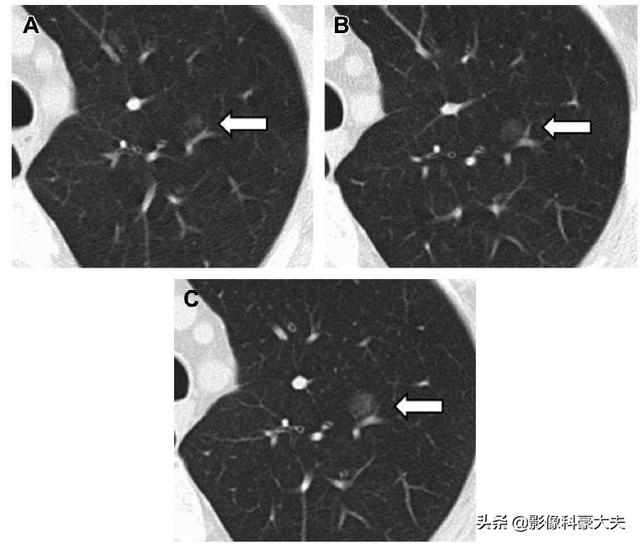

Es handelt sich um einen Fall in der Literatur, bei dem ein seit sechs Jahren wachsender und immer größer werdender Glasknoten operativ als Adenokarzinom in situ diagnostiziert wurde, das weder metastasiert noch rezidiviert und dessen Entfernung eine Heilung darstellt.

Im Allgemeinen ist es bei einigen sehr kleinen mikroskopischen Lungenkarzinomen, die eine hohe diagnostische Ausrüstung und Technik erfordern, notwendig, dieAnspruchsvolle Beobachtung nach dem Wiederaufbau für mehr DetailsDie Niedrigdosis-Spiral-CT ist nicht in der Lage, diese Art von Präzision zu erreichen.